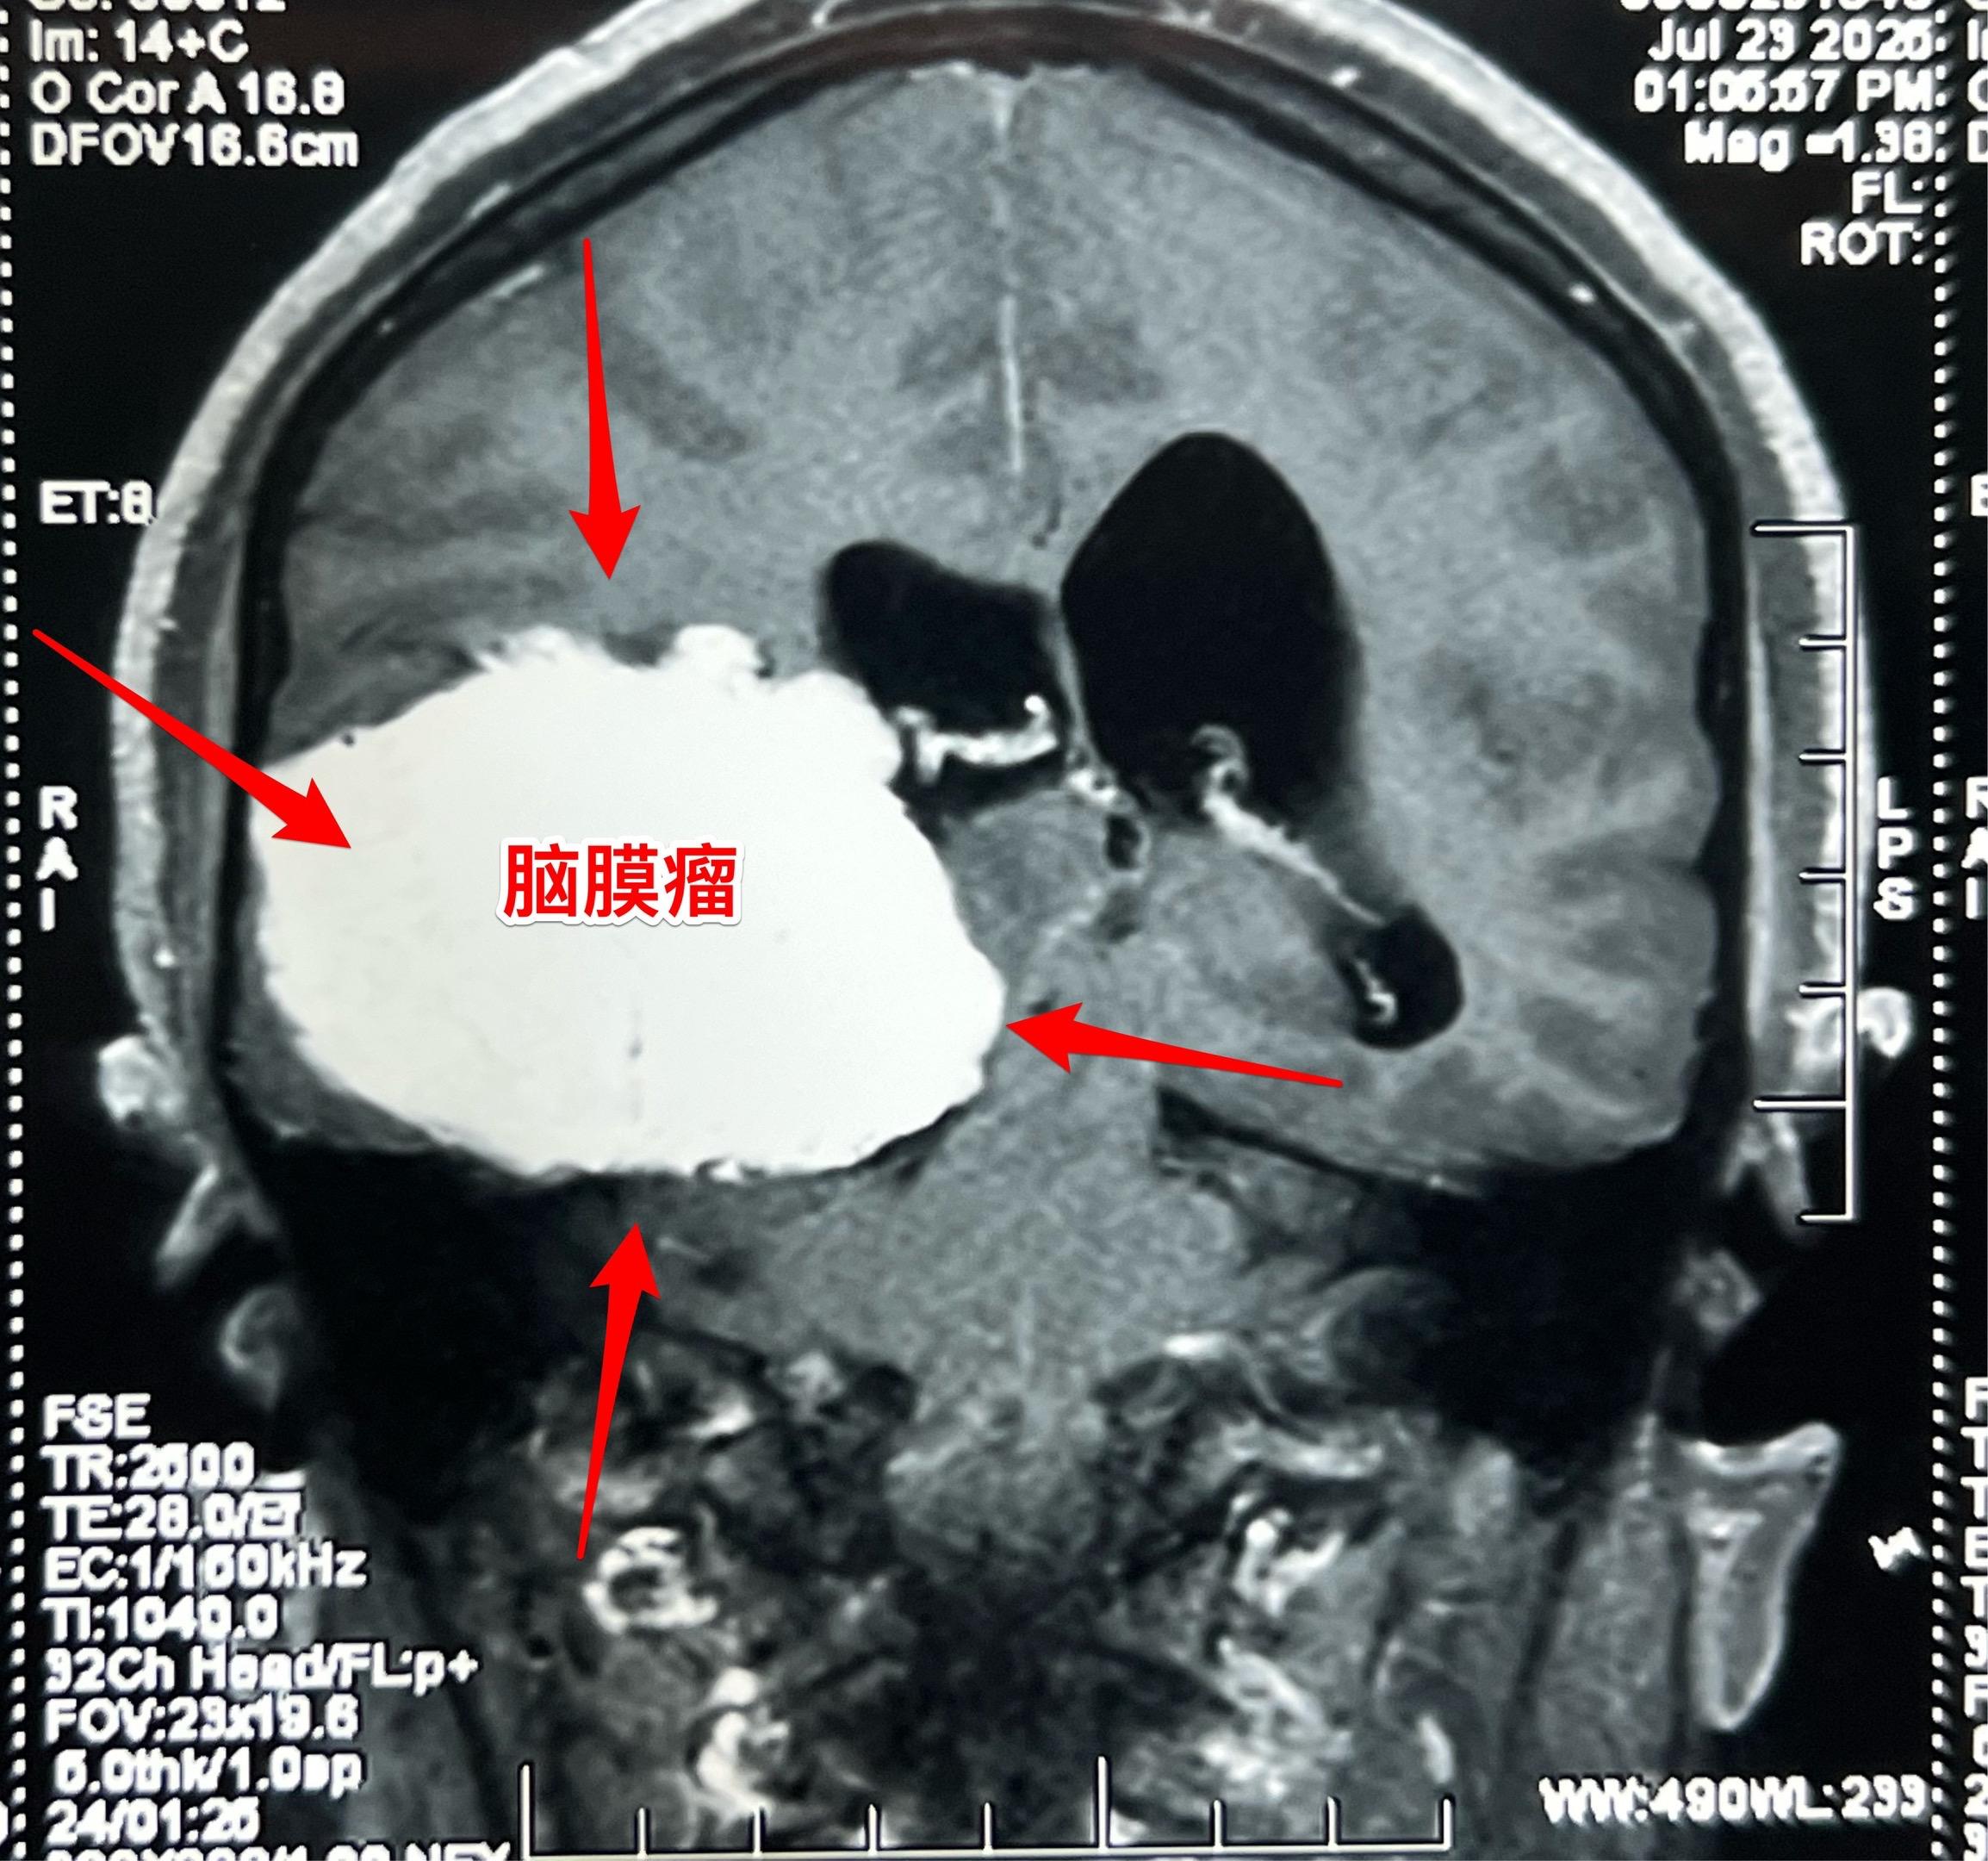

藏族牧民脑肿瘤被发现时像鸡蛋一样大。青海省黄南州藏族牧民,43岁,女性,平时以放养牦牛为生,家里有一百多头牦牛,她夫妻二人完全不能说汉语。 她头痛五年了,视力下降一年,迟迟没有就医,今年七月份因视力很差了才到西医医院检查,发现病根儿是脑膜瘤。如图所示,脑膜瘤像鸡蛋一样大。 发现脑肿瘤后,他们第一步是找活佛预判凶吉,指导治疗方向! 2025年8月1日作了手术,将肿瘤完全切除。希望她能顺利出院!